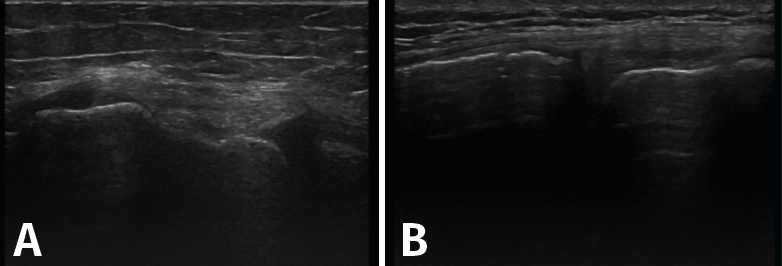

1. Ligamentos

Tanto el ligamento lateral interno (LLI) como el ligamento lateral externo (LLE) pueden ser valorados por ecografía (Figura 7).

Figura 7. Corte coronal de una ecografía de rodilla. A: engrosamiento del ligamento lateral externo en la inserción proximal por un esguince de grado I; B: engrosamiento del ligamento lateral interno.